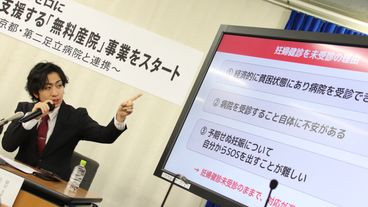

「経済的、精神的不安から、医療機関を受診できずに出産を迎え、社会的に孤立する妊婦が支援を受けられない。このことが、0歳児の虐待死が絶えない背景にある」(フローレンスの駒崎会長)

背景には、虐待や貧困があることも。「型にはめるのではなく、彼女たちの考えを尊重しながら、安心できる場所を作っていきたい」